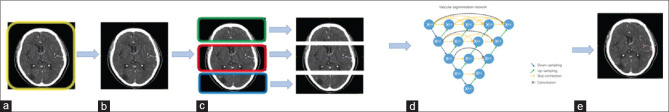

Acute ischemic stroke (AIS) condition assessment and clinical prognosis are significantly influenced by the compensatory state of cerebral collateral circulation. A standard clinical test known as single-phase computed tomography angiography (sCTA) is useful for quickly and accurately assessing the creation or opening of cerebral collateral circulation, which is crucial for the diagnosis and treatment of AIS. To improve the clinical application of sCTA in the clinical assessment of collateral circulation, we examine the present use of sCTA in AIS in this work.